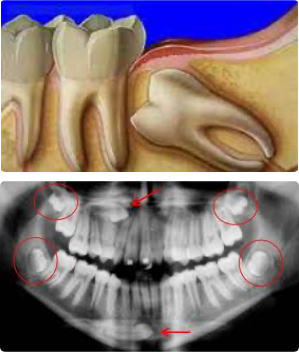

Os implantes dentários são pinos de titânio introduzidos no osso e visam substituir uma ou várias raízes dos dentes perdidos, possibilitando a confecção de dentes sobre estes implantes, devolvendo a mastigação e estética perdidas, podem ser indicados para repor a perda de todos os dentes, de alguns ou de apenas um dente.

Os Implantes dentários são instalados por uma cirurgia simples, rápida e indolor. Como são substitutos de raízes, posteriormente a cirurgia será fixada sobre o implante dentário uma coroa dentária (dente), para então recuperar a mastigação e estética do paciente.

Em geral, leva-se 3 a 6 meses para que o implante dentário cicatrize, antes da colocação do dente definitivo. Neste período de cicatrização, o paciente geralmente utiliza uma prótese dentaria provisória.